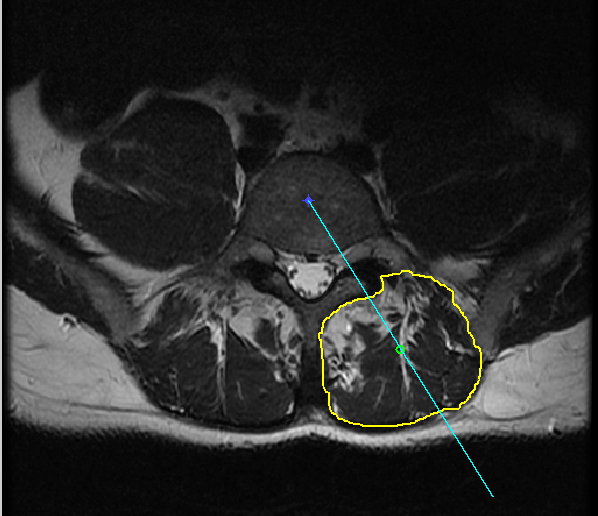

2.6 Fragmenting ES muscles

The next step is to quantify fat in fragmented regions of the erector spinae (ES) muscles. The segmented muscles could be sub-divided into many regions. We have subdivided the segmented muscles into six regions with reference to the centre of the spinal column, as shown in Figure 8 and Figure 9. The use of six fragments was based solely on visual observation by a clinical biomechanist and clearly needs further research. Generally, the segmented muscle region is irregularly shaped. The boundary points are extracted and used to sub-divide the region into smaller segments. After obtaining the various segments, the fat content percentage in each segment is calculated.

Step 2: A radial line from the centre of the spinal column c(x,y)𝑐𝑥𝑦c(x,y), which passes through the centroid of the segmented muscle region and that bisects the ES muscles is plotted, as shown in Figure 7.

Figure 7: Input image with the radial line from the centre of spinal column (Right Erector Spinae Muscles).

Step 3: Considering the radial line as vector v1𝑣1v1 and a horizontal line through the centre of the spinal column c(x,y)𝑐𝑥𝑦c(x,y) as vector v2𝑣2v2, the angle (θ)𝜃(\theta) between the vectors v1𝑣1v1 and v2𝑣2v2 is calculated.

Step 4: The angle (θ)𝜃(\theta) is used to identify, whether the segmented muscle region lies either on the right side or the left side of the spinal column. If the angle (θ)𝜃(\theta) is less than 90osuperscript90𝑜90^{o} the segmented muscle region is considered to be on the right side and it is rotated by angle (θ)𝜃(\theta) in the counter-clockwise direction as shown in Figure 8, else the segmented muscle region is considered to be on the left side and it is rotated by an angle (180θ)180𝜃(180-\theta) in the clockwise direction as shown in Figure 9.